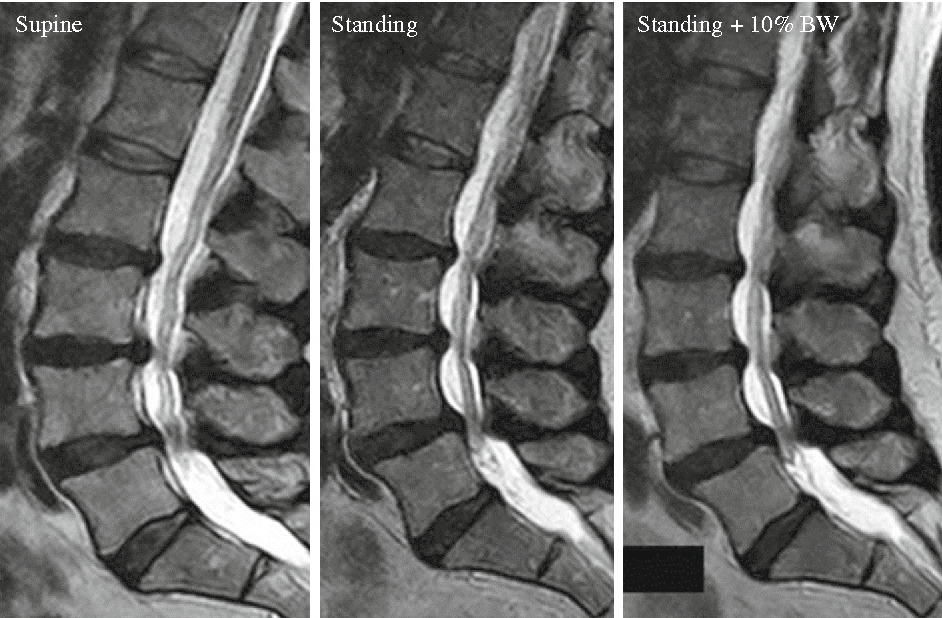

MR çekimi, röntgen , ultrason veya BT taramaları gibi diğer görüntüleme testlerinden farklı türde bir görüntü sağlar. Lomber omurganın MR ı kemikleri, diskleri, omuriliği ve sinirlerin geçtiği omur kemikleri arasındaki boşlukları gösterir.